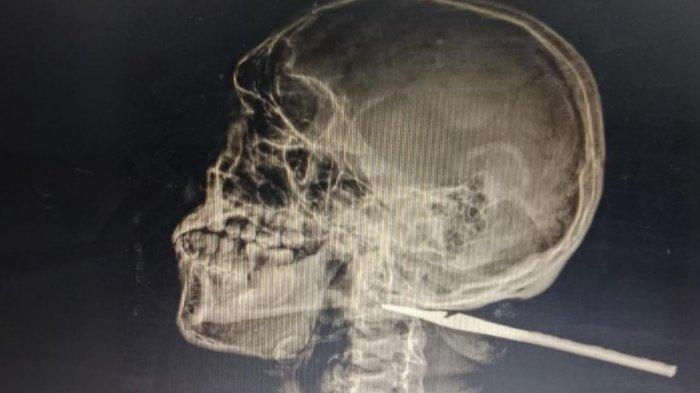

Hasil rontgen korban di Rumah Sakit Siloam, Jumat (3/1/2024).

Korban kemudian dirujuk ke Ambon menyusul anak panah menembus hingga ke tulang tenggorokan.